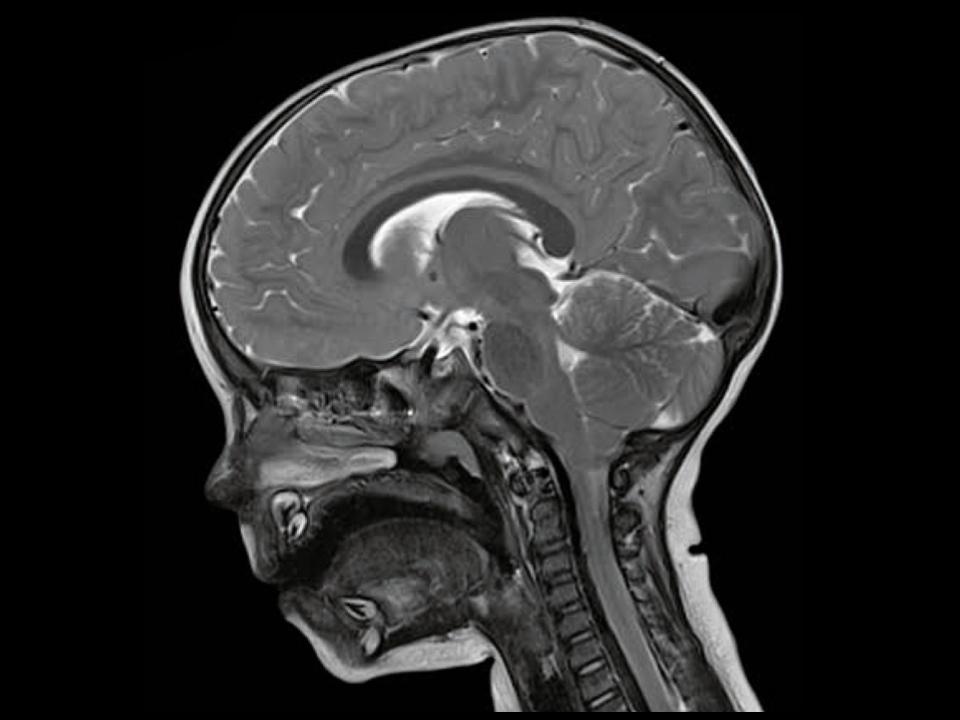

Magnetic resonance imaging (MRI)1 is often used to depict internal organs. Unlike other imaging procedures, the MRI scanner works with a magnetic field and radio waves, which means there is no radiation exposure. An MRI examination can only be conducted using a lot of technology and a large machine. This procedure is unfamiliar to children and can cause a variety of reactions. While one child will be excited and curious about the machine, others will be afraid of spending time in the treatment room.